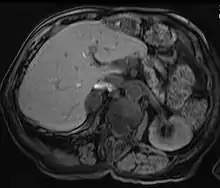

Hepatic adenomas are a rare benign tumour of the liver, which may present with hepatomegaly or other symptoms.